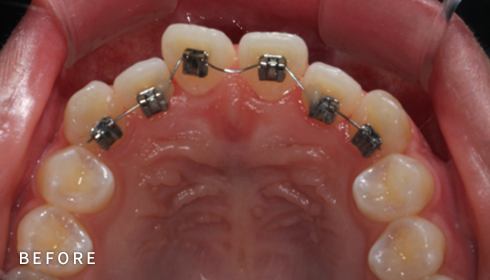

설측교정은 치아 안쪽(설측면)에 초소형 장치로 보이지 않게

아름다운 미소를 만드는 고난이도 프리미엄 교정 치료입니다.

난이도가 높은 만큼 풍부한 진료 경험이 중요합니다.

강남에서 다년간 설측교정에 특화된 경험을 바탕으로,

3D 디지털 기술을 활용한 맞춤 설계, IDBS방식을 통한

정밀하고 불편감 없는 치료를 제공합니다.